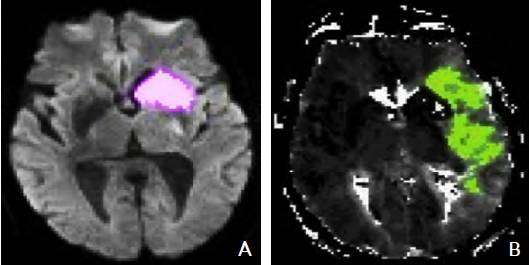

MRI PWI常采用动态磁敏感对比增强技术,通过对比剂团注追踪技术进行动态增强扫描,依靠对比剂磁化率改变引起信号变化的原理成像。经处理后可得出相应灌注成像的参数如CBF、CBV、MTT及TTP等。研究表明,CBF下降和MTT延长是组织缺血的相对敏感指标,但存在过分估计最终梗死体积的可能性;TTP图像上脑灰质、白质之间无明显区别,可以清楚显示病变的范围和边界。虽然目前识别缺血半暗带的方法有多种,但MRI DWI与PWI不匹配区是急诊过程中判断缺血半暗带较切合实际的方法(图4)。一项回顾性研究认为,PWI的病灶面积是DWI病灶面积的2.6倍时早期再灌注的治疗效果最好。

图4 磁共振成像DWI-PWI不匹配区影像 注:A:磁共振DWI序列:高信号的梗死区(粉色标记区);B:磁共振PWI序列:梗死区周围的缺血半暗带(绿色标记区)。DWI:弥散加权成像;PWI:灌注加权成像